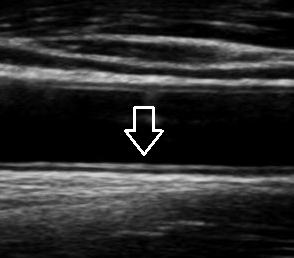

초음파를 통해 혈관 내막-중막 두께(IMT)를 측정함으로써 초기 단계의 동맥경화 여부를 파악할 수 있습니다. IMT가 정상 범위를 벗어나 두꺼워져 있다면 전신 동맥경화 위험이 높다고 판단합니다.

경동맥 협착은 혈관 내강이 좁아져 뇌로 가는 혈류가 감소하는 상태입니다. 협착 정도가 경미한 경우에는 무증상으로 지나가지만, 일정 수준 이상 진행되면 뇌허혈 증상이나 뇌졸중 위험이 급격히 증가합니다. 경동맥 초음파에서는 협착 부위, 협착률, 혈류 속도 변화를 종합적으로 분석해 위험도를 평가합니다. 일반적으로 협착률이 50% 이상이면 적극적인 관리 대상이 됩니다.